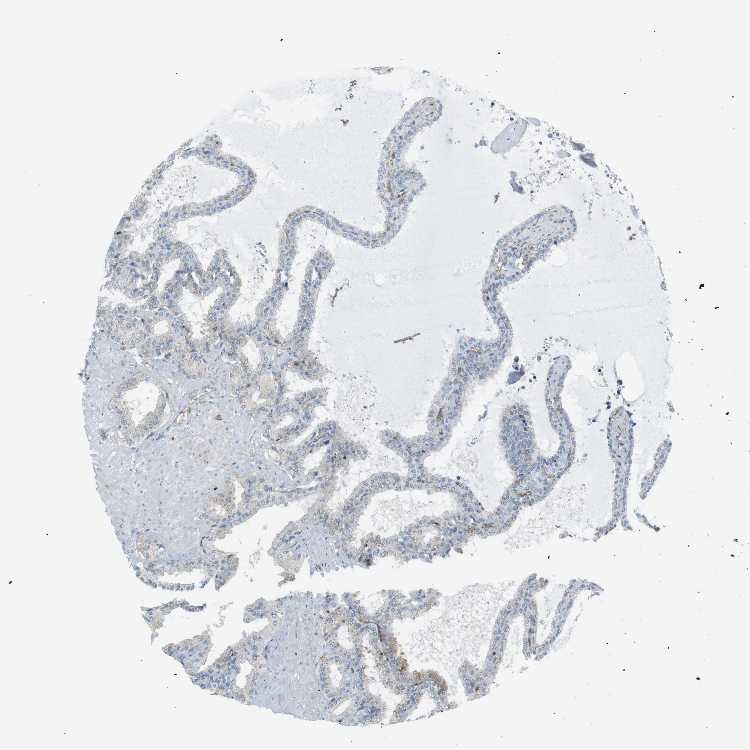

SEMINAL VESICLE - Antibody stainingi

Antibody staining in the annotated cell types in the current human tissue is reported as not detected, low, medium, or high, based on conventional immunohistochemistry profiling in selected tissues. This score is based on the combination of the staining intensity and fraction of stained cells.

Each image is clickable and will lead to virtual microscopy that enables deeper exploration of all samples and also displays staining intensity scores, fraction scores and subcellular localization as well as patient and tissue information for each sample.

Antibody CAB008973Antibody CAB012962

Glandular cells MediumLow